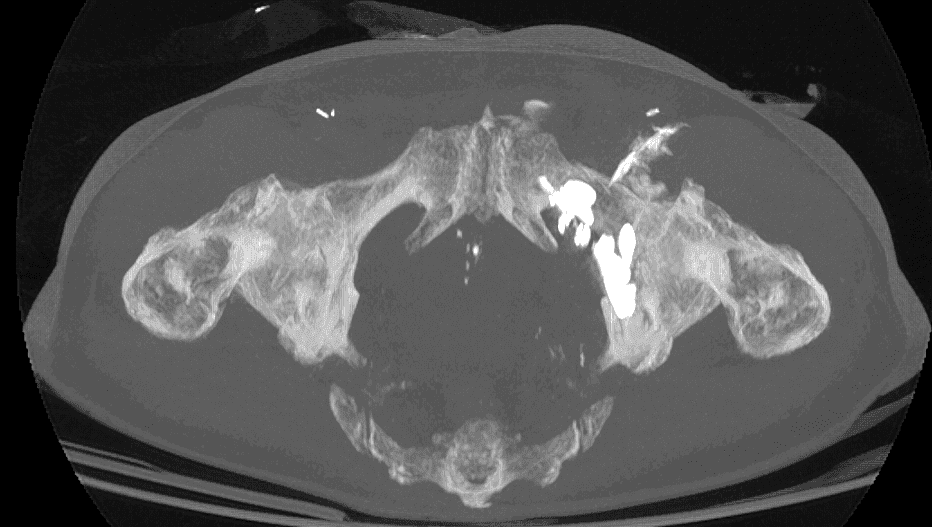

Analyse des images CT pour définir la trajectoire optimale du vissage en fonction du schéma de fracture.

Déterminer des repères anatomiques et la configuration osseuse pour minimiser le risque de pénétration intra-articulaire.

Un contrôle scanner final permet de vérifier la position du vissage et la qualité de la réduction anatomique, garantissant ainsi le succès de l’intervention.